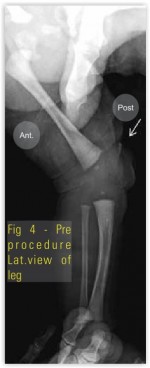

Our case was a preterm (35 weeks) baby boy born by normal vaginal delivery with history of oligohydraminios, presented with extreme hyperextension of left knee with toe almost touching the abdomen (Fig.1 ) with associated anomalies present; patient had CDH(Fig.3 and 4), Quadriceps contracture(Fig.2 ) and CTEV in the same involved lower limb. Left hip showed acetabular dysplasia. The affected left side shows presence of increase in depth of iguinal fold, abduction is limited at the left hip, the Ortolani and Barlow test was positive. Telescopic sign was positive. The feet on both side were inverted to about 30 degree and foot was pointing down wards. The ankle was in equines the feet were supinated and adducted, dorsiflexion beyond 90 degree was not possible. Tibia was normal and was not having an internal torsion. Passive stretching followed by above knee (toe to groin) POP splints was used from the first day. The basic principal of correction of adduction first followed by varus & then equines is followed. The splints were changed every seventh day with gradual bending. In about a month time knee flexion range of movement about 70 degree was achieved. There is need to be cautious at this time to avoid excessive & forceful correction as this may lead to damage to epiphysis & future growth abnormalities. As mentioned by Nogi et al, when there is concurrent presence of DDH with this knee abnormality then knee problem should be treated first as good knee movements can help with correction of hip abnormality [19]. In three months’ time, the left knee adopted a normal shape and position. The splints were discontinued and the mother was advised to continue passive stretching. The CDH was treated by abduction splints (wearing of double diapers) for six weeks. CTEV was treated with serial manipulation and POP Casts. A follow up at the age of one year showed normal position of both knees(Fig.5) as well as both hips.